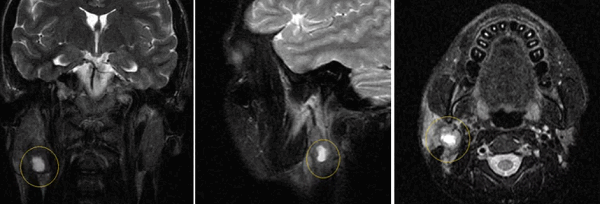

МРТ слюнных желез с контрастом

МРТ с контрастом дает возможность на ранних стадиях выявить опухолевые образования в структуре слюнных желез, определить их размеры, локализацию, форму, строение, степень васкуляризации (кровоснабжения). Это требуется, в том числе, перед проведением хирургического лечения для определения объемов вмешательства и стратегии терапии, биопсией. На основании данных МРТ с контрастом можно сделать предварительный вывод о злокачественности или доброкачественности новообразования.

Применение обследования помогает обнаружить аденокарциному слюнной железы - злокачественную опухоль, склонную к быстрому прогрессированию, прорастанию близлежащих тканей. Онкология чаще обнаруживается случайно, так как не имеет специфических внешних признаков.

Сиалография при раке

Отечность, онемение жевательной мышцы при открывании рта, боль челюсти во время жевания пищи могут появляться при раке. Процент встречаемости доброкачественных железистых образований выше, чем злокачественных аналогов.

Компьютерная сиалография с 3D-реконструкцией позволяет изучить образование в пространственном представлении. Диагностическая информация важна специалистам для определения, сколько живут люди с опухолями слюнной железы. Чем крупнее злокачественное образование, тем выше вероятность летального исхода в ближайшие 5-10 лет. Только ранняя верификация и грамотное хирургическое иссечение опухолевого узла навсегда избавляет от смертельной опасности.